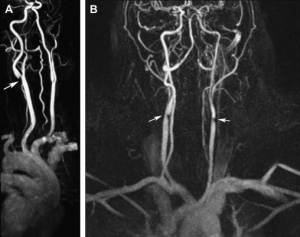

Magnetic Resonance Angiography and Computed Tomographic Angiography

New non-invasive or minimally invasive methods such as magnetic resonance angiography (MRA) (Figure 9) and computed tomographic angiography (CTA) (Figure 10) are increasingly used as second-line investigative tools after duplex ultrasound for carotid stenosis and have gradually replaced DSA .[20]

A review of carotid MRA performance data found that for the diagnosis of 70–99% carotid stenosis, MRA superior pooled sensitivity (95%) and specificity (90%) to conventional DSA.[24] For the detection of complete occlusions, MRA showed similar performance to duplex ultrasound, with a sensitivity of 98% and a specificity of 100%. However, MRA has some limitations, including claustrophobia, pacemakers, obesity, and metallic stents or implantable defibrillators.

Potential advantages of MRA and CTA over conventional angiography include their abilities to allow better carotid plaque characterization and identification and to simultaneously evaluate for cerebrovascular accident.[25] The combined use of MRA, CTA, and doppler ultrasound improves diagnostic accuracy for high-grade symptomatic carotid stenoses and minimizes the need for invasive carotid arteriography. Disadvantages of CTA include the necessity of administering a nephrotoxic iodinated contrast agent and ionizing radiation and the potential for artifacts related to heavily or circumferentially calcified arterial walls.